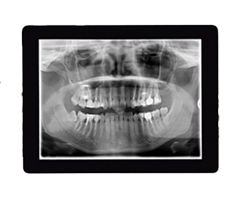

Digital X-Rays

When it comes to diagnosing and planning your treatment, digital X-rays give us a detailed view of your teeth, jawbone, and facial structure—all with significantly less radiation than traditional film X-rays.

Why do we use digital X-rays?

- Lower Radiation Exposure: Digital X-rays use up to 90% less radiation than conventional X-rays, prioritizing your safety.

- Immediate Results: Images appear instantly on our monitors, so we can review and explain them with you in real-time.

- Eco-Friendly: No film or chemicals means a more sustainable and environmentally friendly process.

- Better Diagnostics: High-resolution images allow us to detect concerns early, monitor growth and development, and plan treatments with greater confidence.

With digital X-rays, we can provide accurate, high-quality care while keeping your safety and comfort front and center.